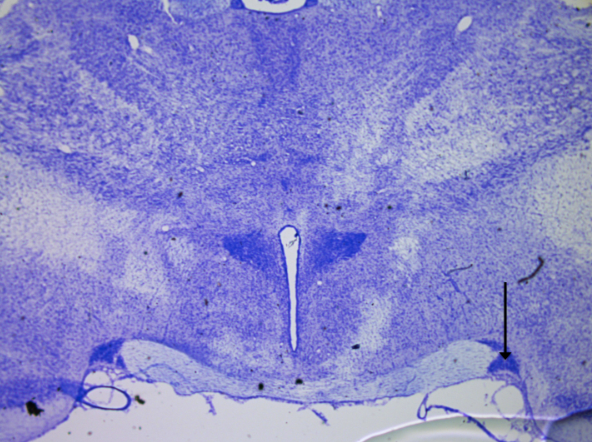

2

New cards

Hippocampus CA1

knowt flashcard image